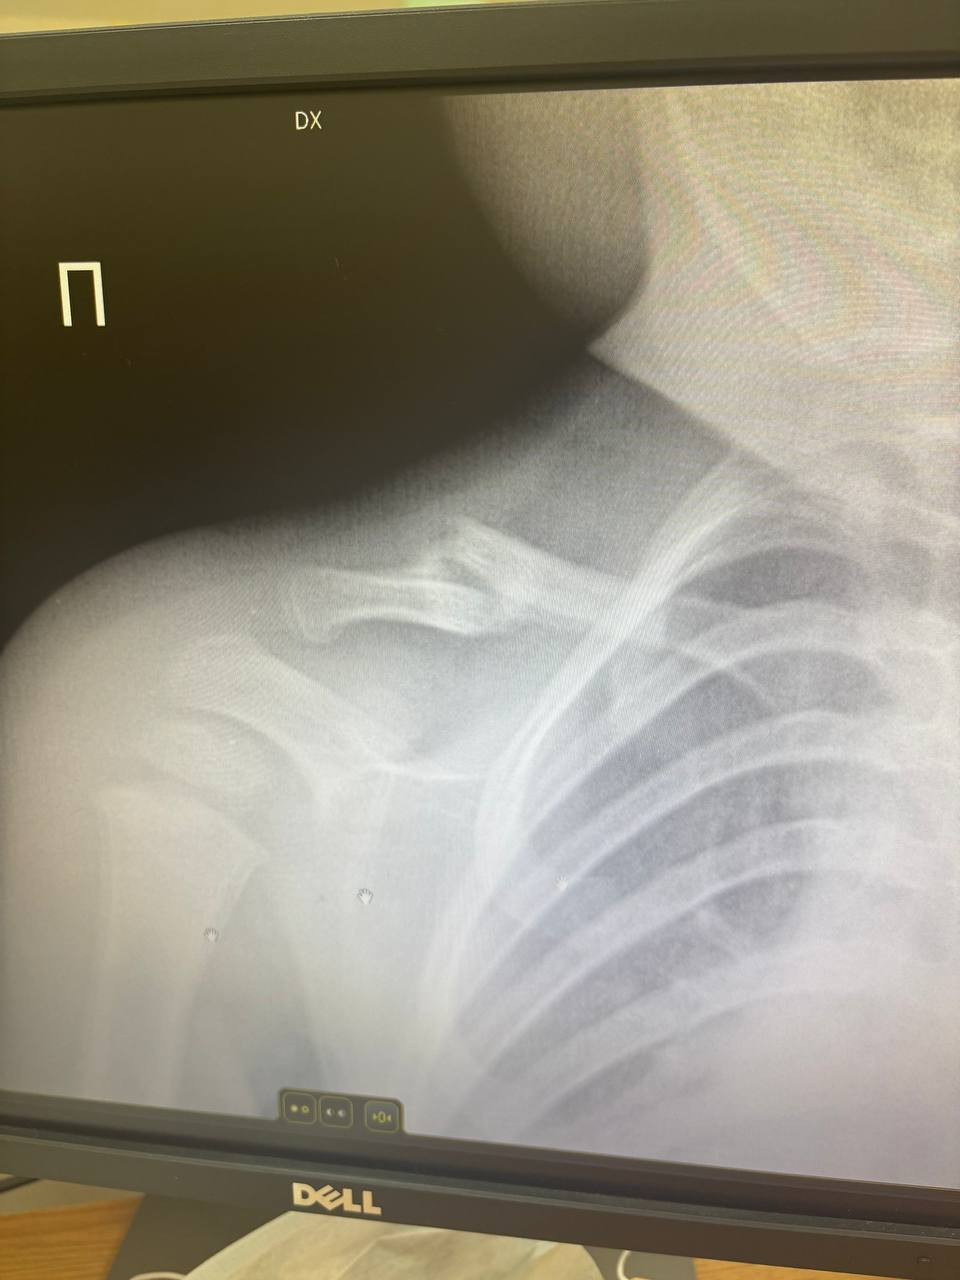

Травма: перелом правой ключицы

Лечение: повязка дезо 3 недели

Идет уже 24й день как носим повязку, сегодня сделали снимок и особых изменений не увидели

Просто смотря на снимок и не имея знаний в хирургии мне кажется что тут все очень плохо

Здравствуйте. По снимку действительно видно перелом ключицы, но для ребёнка в возрасте 1 года 3 месяцев это довольно частая травма и процесс сращения может быть не сразу заметен на рентгене, особенно если перелом без смещения. У малышей кость быстро регенерирует и зачастую образуется костная мозоль позже визуально чем у взрослых. Главное это отсутствие боли, отёка и подвижности в месте перелома. Повязку продолжают носить до 4 недель, затем  контроль.

Здравствуйте. Рентген показывает перелом и хотя явной костной мозоли пока не видно, у детей часто сращение идёт активно, но визуально проявляется позже. Однако если есть сомнения или клинически что-то беспокоит (болезненность, деформация), стоит повторить снимок через 1-2 недели и проконсультироваться очно. Иногда требуется более длительная иммобилизация или контроль у детского травматолога.